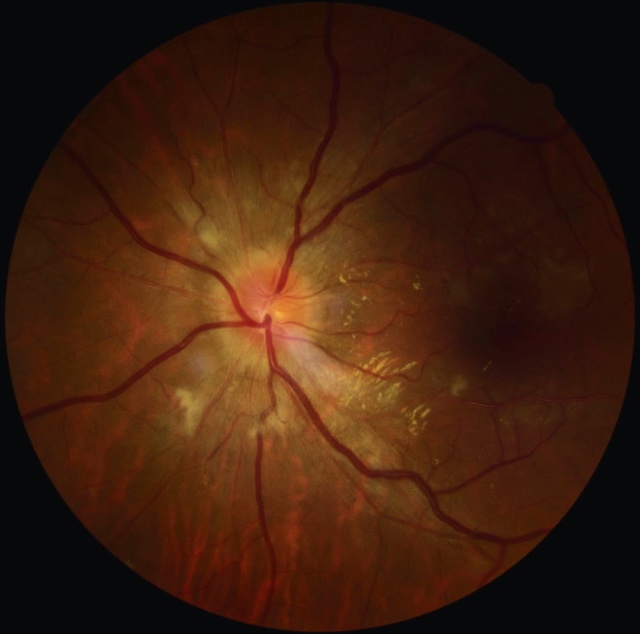

b Occlusion de la veine centrale de la rétine (OVCR) ou d’une de ses branches (fig. 8.7 à fig. 8.10 et e-fig. 8.11)

Photographie ultra-grand champ d’un fond d’œil droit, réalisée en imagerie rétinienne à large champ, montrant une occlusion de la veine centrale de la rétine. Le disque optique apparaît flou, congestionné et légèrement bombé, témoignant d’un œdème papillaire. Les veines rétiniennes sont visiblement dilatées et tortueuses sur tout le réseau vasculaire, avec de nombreuses hémorragies diffuses réparties dans les quatre quadrants, en nappe et en flammèches. L’arrière-plan rétinien présente des zones de stase veineuse et un aspect diffusément rouge sombre, évoquant un engorgement massif. Cette image traduit un tableau classique d’occlusion veineuse centrale avec retentissement aigu sur la perfusion rétinienne.